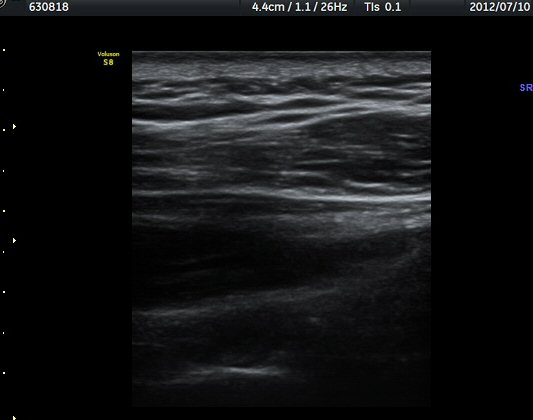

ÈíÀÎ 50ÀÏ ÈÄ ÃÊÀ½ÆÄ°Ë»ç¿¡¼­ ³¶Á¾ Å©±â °¨¼Ò°¡ ¶Ñ·ÈÇÏ´Ù(±×¸² 9, 10).